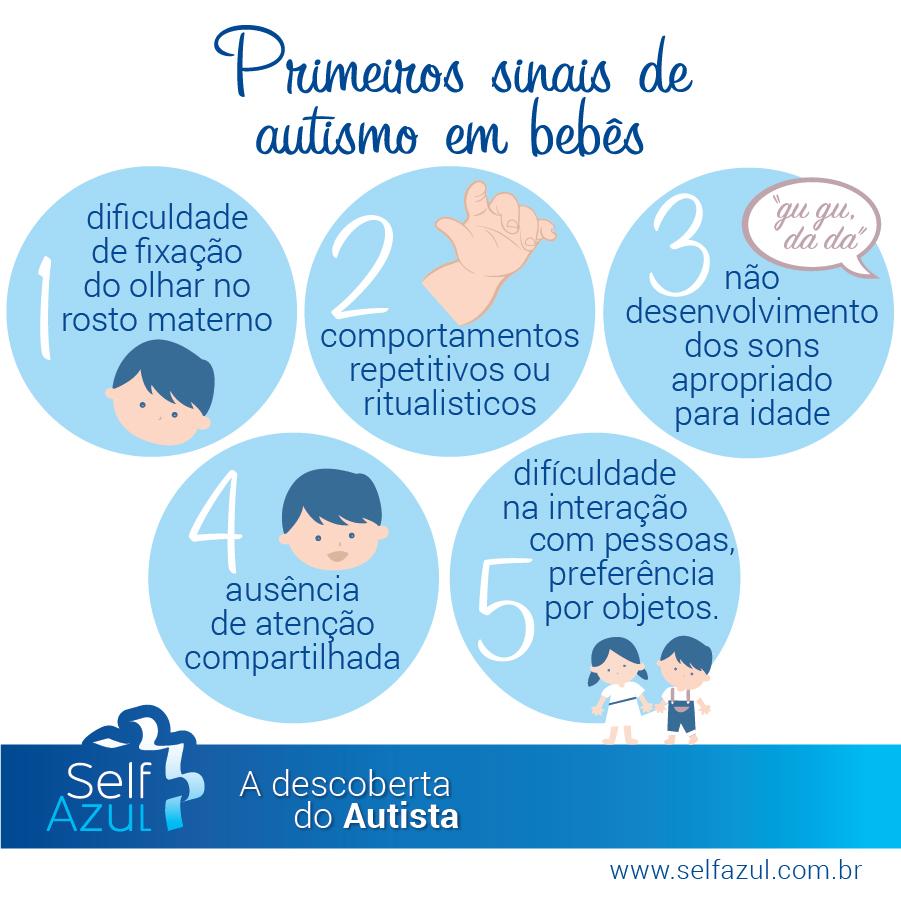

SelfAzul on X: Veja quais são os primeiros sinais de #autismo em bebês. #infográfico #TEA #luzAzul #selfAzul #autismoerealidade / X04 abril 2025

SelfAzul on X: Veja quais são os primeiros sinais de #autismo em bebês. #infográfico #TEA #luzAzul #selfAzul #autismoerealidade / X04 abril 2025 -